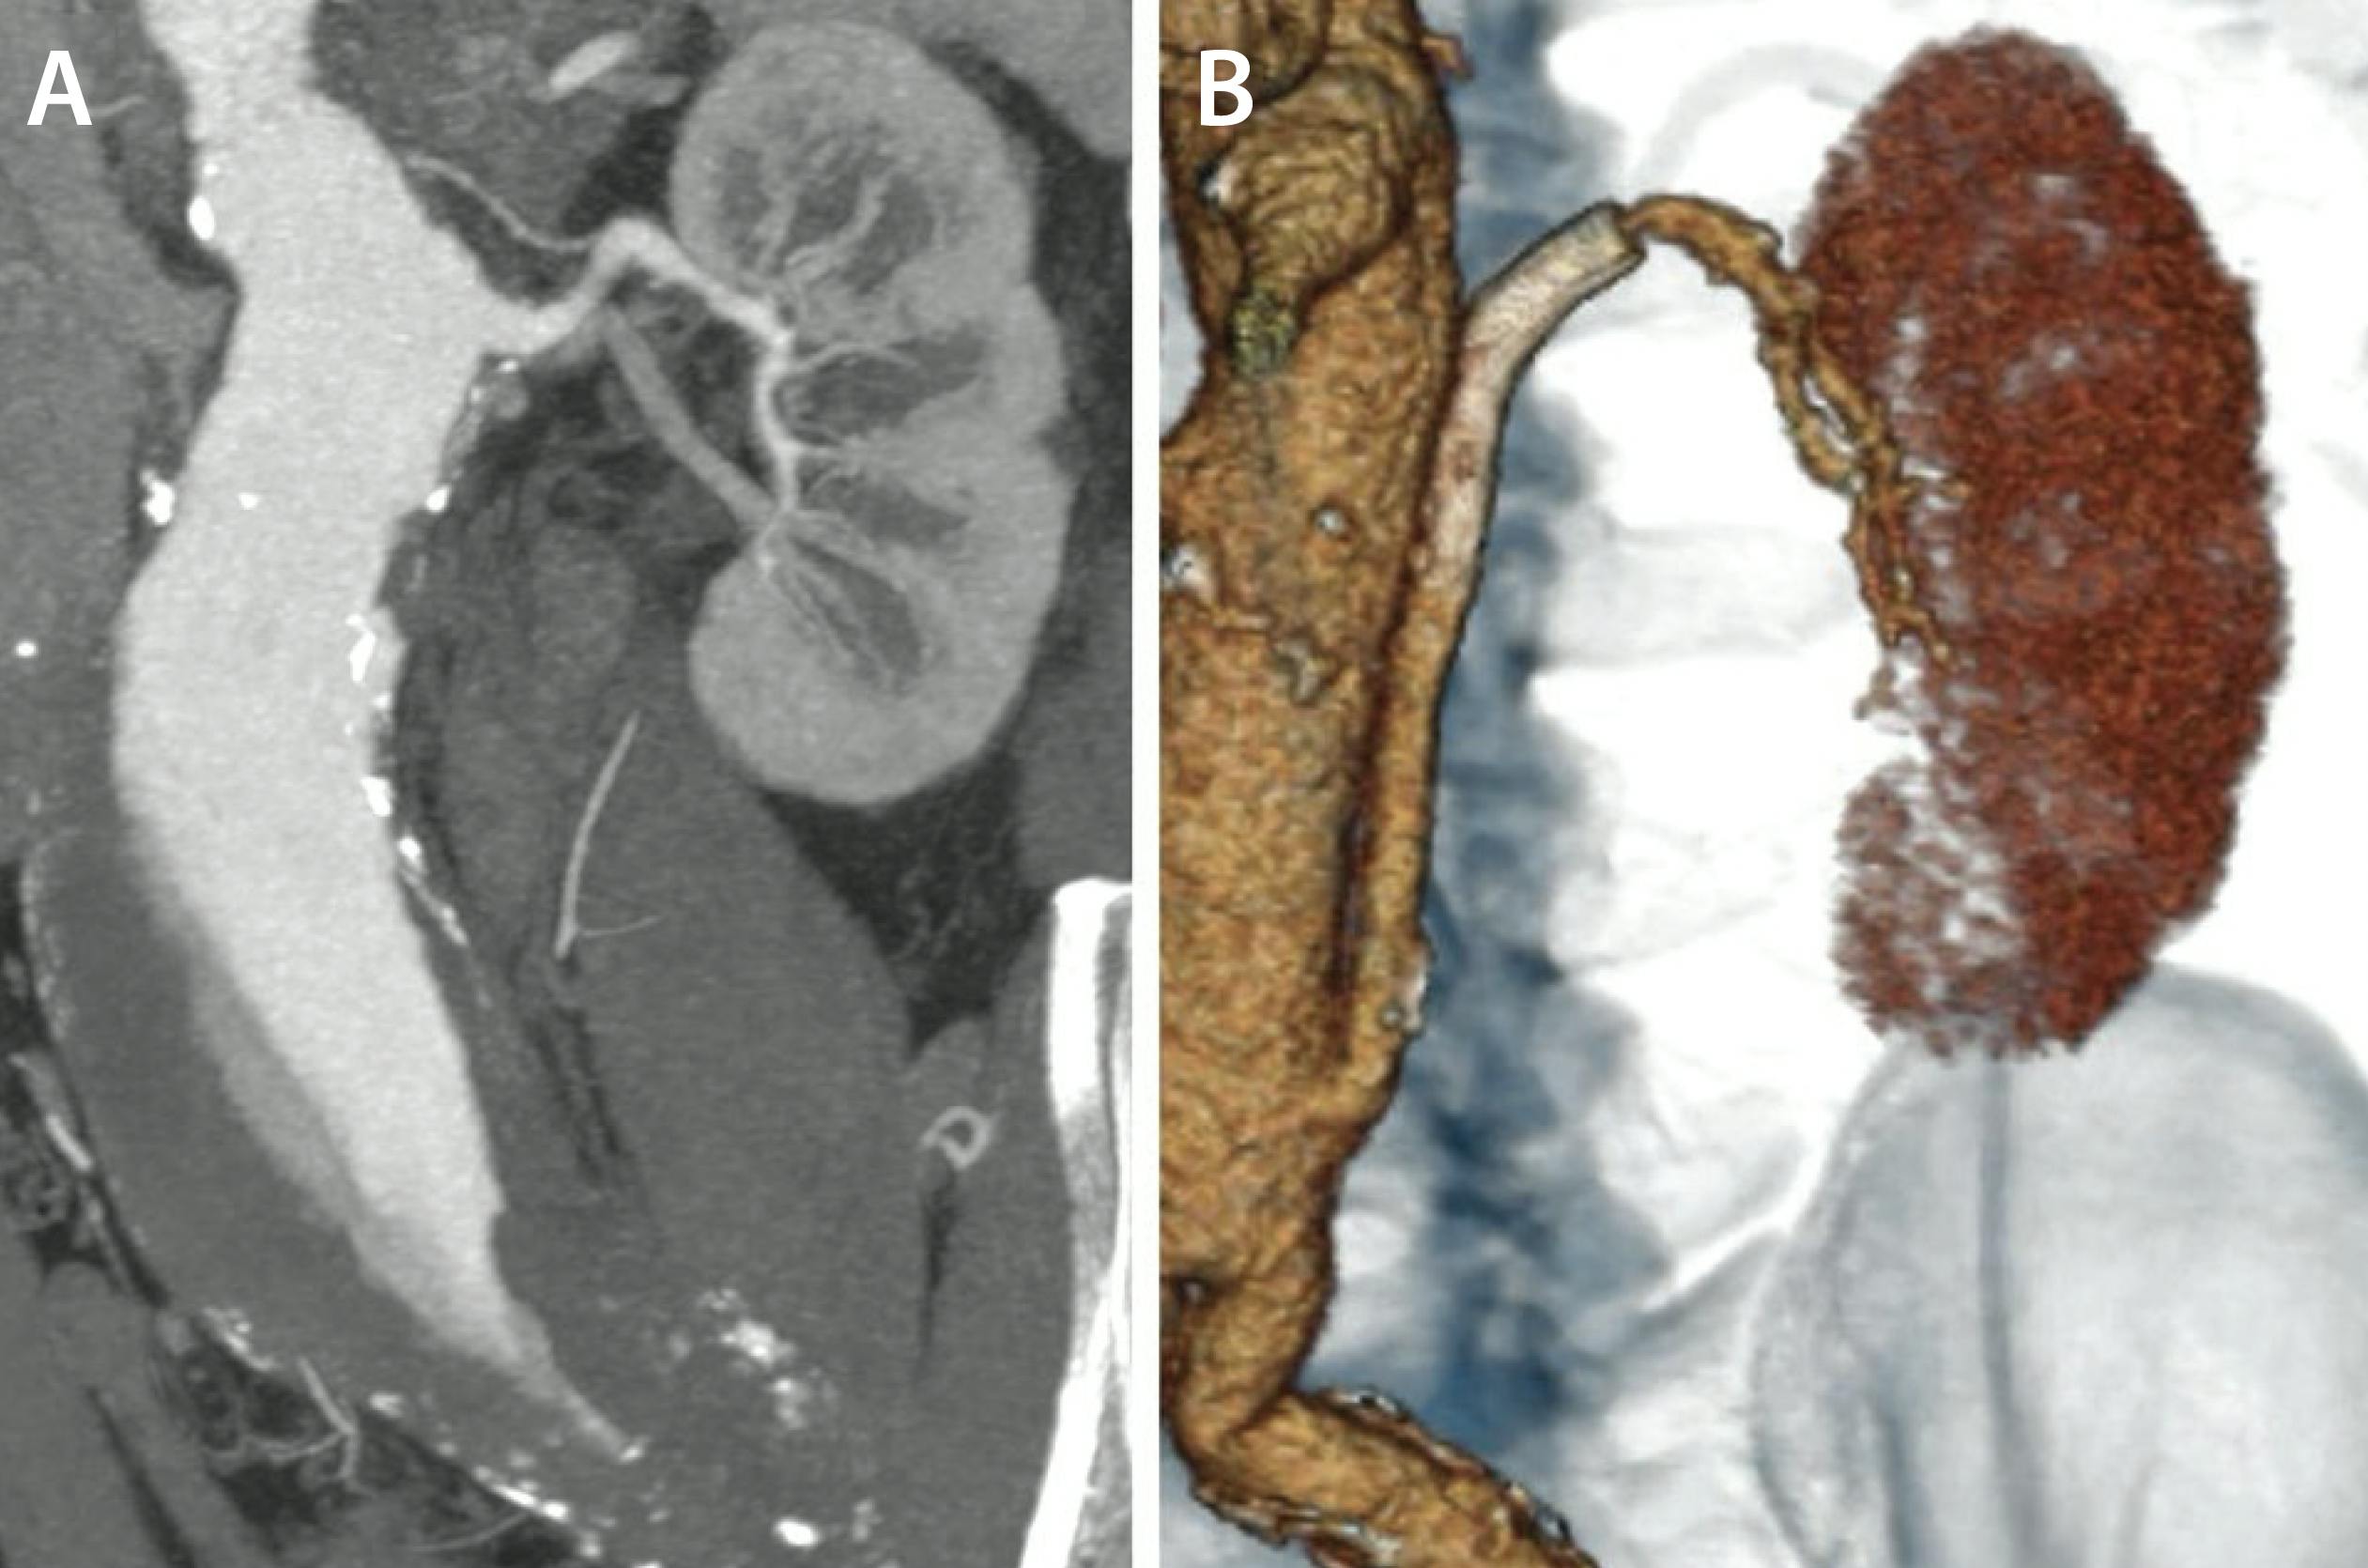

A man in his mid 70s with multiple atherosclerotic risk factors and a history of pararenal aortic aneurysm repair 6 years earlier presented with a 1-day history of left flank pain. The prior repair consisted of an aortobisiliac bypass and surgical debranching of the left renal artery using a Gore® hybrid vascular graft (Gore & Associates) (Figure 1).

Figure 1. Preoperative multiplanar reconstruction of the pararenal aortic aneurysm (A). Postoperative 3D reconstruction showing the aortobisiliac bypass and surgical debranching of the left renal artery using a Gore® hybrid vascular graft (B).

Laboratory tests revealed acute kidney injury (KDIGO [Kidney Disease Improving Global Outcomes] stage 1) with a serum creatinine of 1.9 mg/dL and an estimated glomerular filtration rate of 38 mL/min/1.73 m2 (Cockcroft–Gault formula). CTA demonstrated complete thrombosis of the left aortorenal bypass, with no arterial phase enhancement but preserved collateral-supported perfusion on the venous phase (Figure 2).

Figure 2. Arterial (A) and venous (B) phases of contrast-enhanced CTA demonstrating thrombosis of the left aortorenal bypass with preserved enhancement during the venous phase.